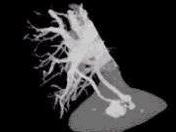

请看一组肺血管的CT增强图像,考虑最可能的诊断为 ( )A、肺动脉钙化B、肺动脉破裂C、肺动脉狭窄D、肺动脉扩张E、肺动静脉畸形

问题 请看一组肺血管的CT增强图像,考虑最可能的诊断为 ( )

选项 A、肺动脉钙化 B、肺动脉破裂 C、肺动脉狭窄 D、肺动脉扩张 E、肺动静脉畸形

答案 E